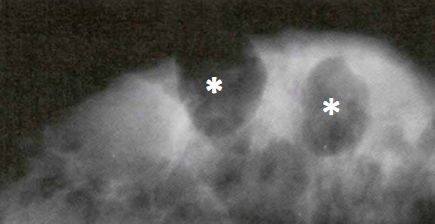

A woman presents with a hard breast lump with irregular borders. She has had surgery on her breast in the past. Mammogram is performed

Fat necrosis